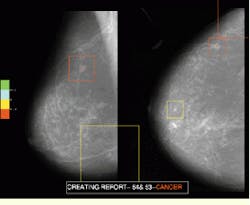

Based on the groupings and the context of the surrounding tissue and the orthogonal view, the second neural network derives a likelihood of cancer present for each ROI. For demonstration purposes, the likelihood of cancer present in different ROIs is represented by overlaying a color-coded symbol on the entire appropriate scanned area in the mammogram image and displaying it on a Silicon Graphics (Boulder, CO) workstation.

FIGURE 4. Red, green, and blue color codes tell radiologists the location and potential for breast cancer in a typical mammogram.